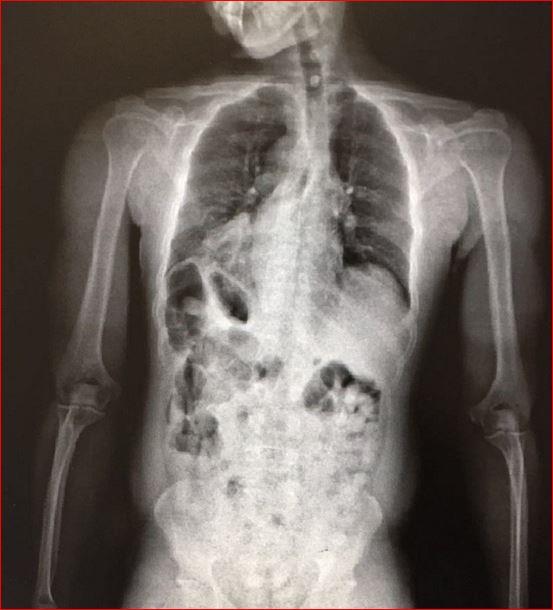

تمكّن جمرك مطار الأمير محمد بن عبدالعزيز في المدينة المنورة في المملكة العربية السعودية، من إحباط تهريب كمية من "الكوكايين" بلغت 936.9 غراماً، عُثر عليها مُخبأة في أحشاء أحد الركاب القادمين إلى المملكة عبر المطار.

وأوضح مدير عام جمرك المطار فيصل الدباغ، أنه عند إنهاء الإجراءات الجمركية لركاب إحدى الرحلات القادمة، اشتبه المراقب الجمركي بأحد الركاب وعلى الفور تم التأكد من حالة الاشتباه وذلك بإحالة الراكب لجهاز فحص الأحشاء بالأشعة، وبالفعل عُثر بداخل أحشاء هذا الراكب على 83 كبسولة صغيرة الحجم تحتوي بداخلها على تلك الكمية من مادة "الكوكائين".